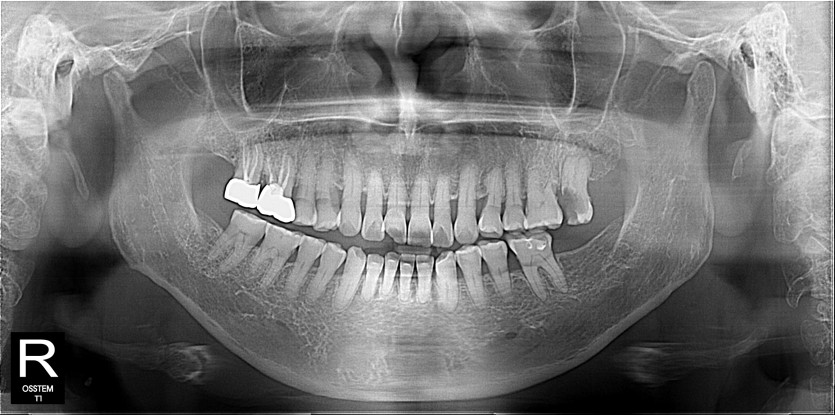

임플란트 사례